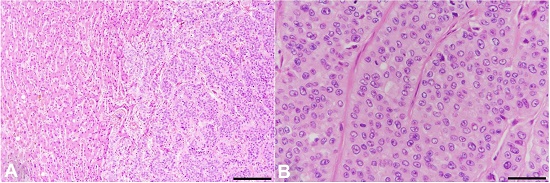

Microscopically, the tumors were composed of neoplastic cells containing abundant eosinophilic cytoplasm and round nuclei. The neoplastic cells formed solid nests and trabecular structures with central necrosis, with a distinct hepatoid morphology (Figure 5).

They were well circumscribed and did not display capsulation. Microscopically, they demonstrated almost the same morphology as the lung lesions. Interestingly, the trabecular structures were even more marked in the liver lesions than in the lung lesions, as is seen in moderately differentiated hepatocellular carcinoma (Figure 8). There was no evidence of cirrhosis.